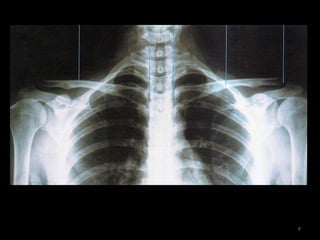

Incidência AP: Articulação acromioclavivular  bilateral (com e sem peso) 10

11

Sem peso12

Com peso13